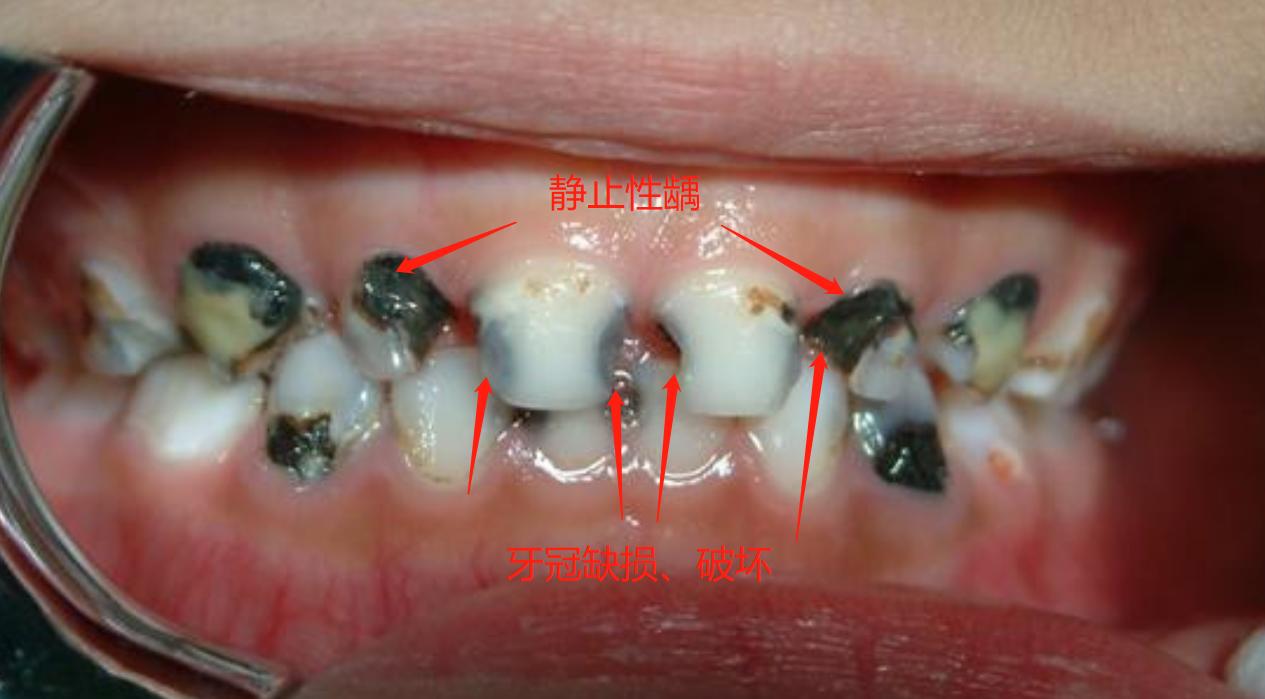

- 龋病发生时,乳牙颜色会呈现两种典型变化。其一,表面光洁、呈黑褐色,称为静止龋;其二,表面松软、呈黄褐色,称为湿性龋(急性龋)。前者进展缓慢,而后者往往会快速、广泛的引起乳牙龋坏!

- 龋病发生时,乳牙会出现破损。其中,门牙的邻面、唇面是龋损的高发部位。当宝贝刷牙漱口后,爸爸妈妈可以仔细观察,门牙这两个位置是否有缺口。如果牙冠表面不光滑、有凹陷,那很可能已有蛀牙!